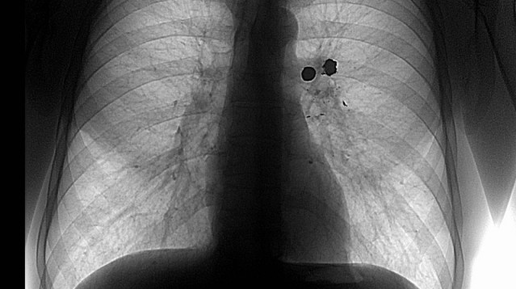

Пневмоторакс. Что это такое ? И чем он опасен ?

При пневмотораксе организм начинает страдать от гипоксии ( нехватке кислорода) и нарушении обмена веществ (метаболизм).